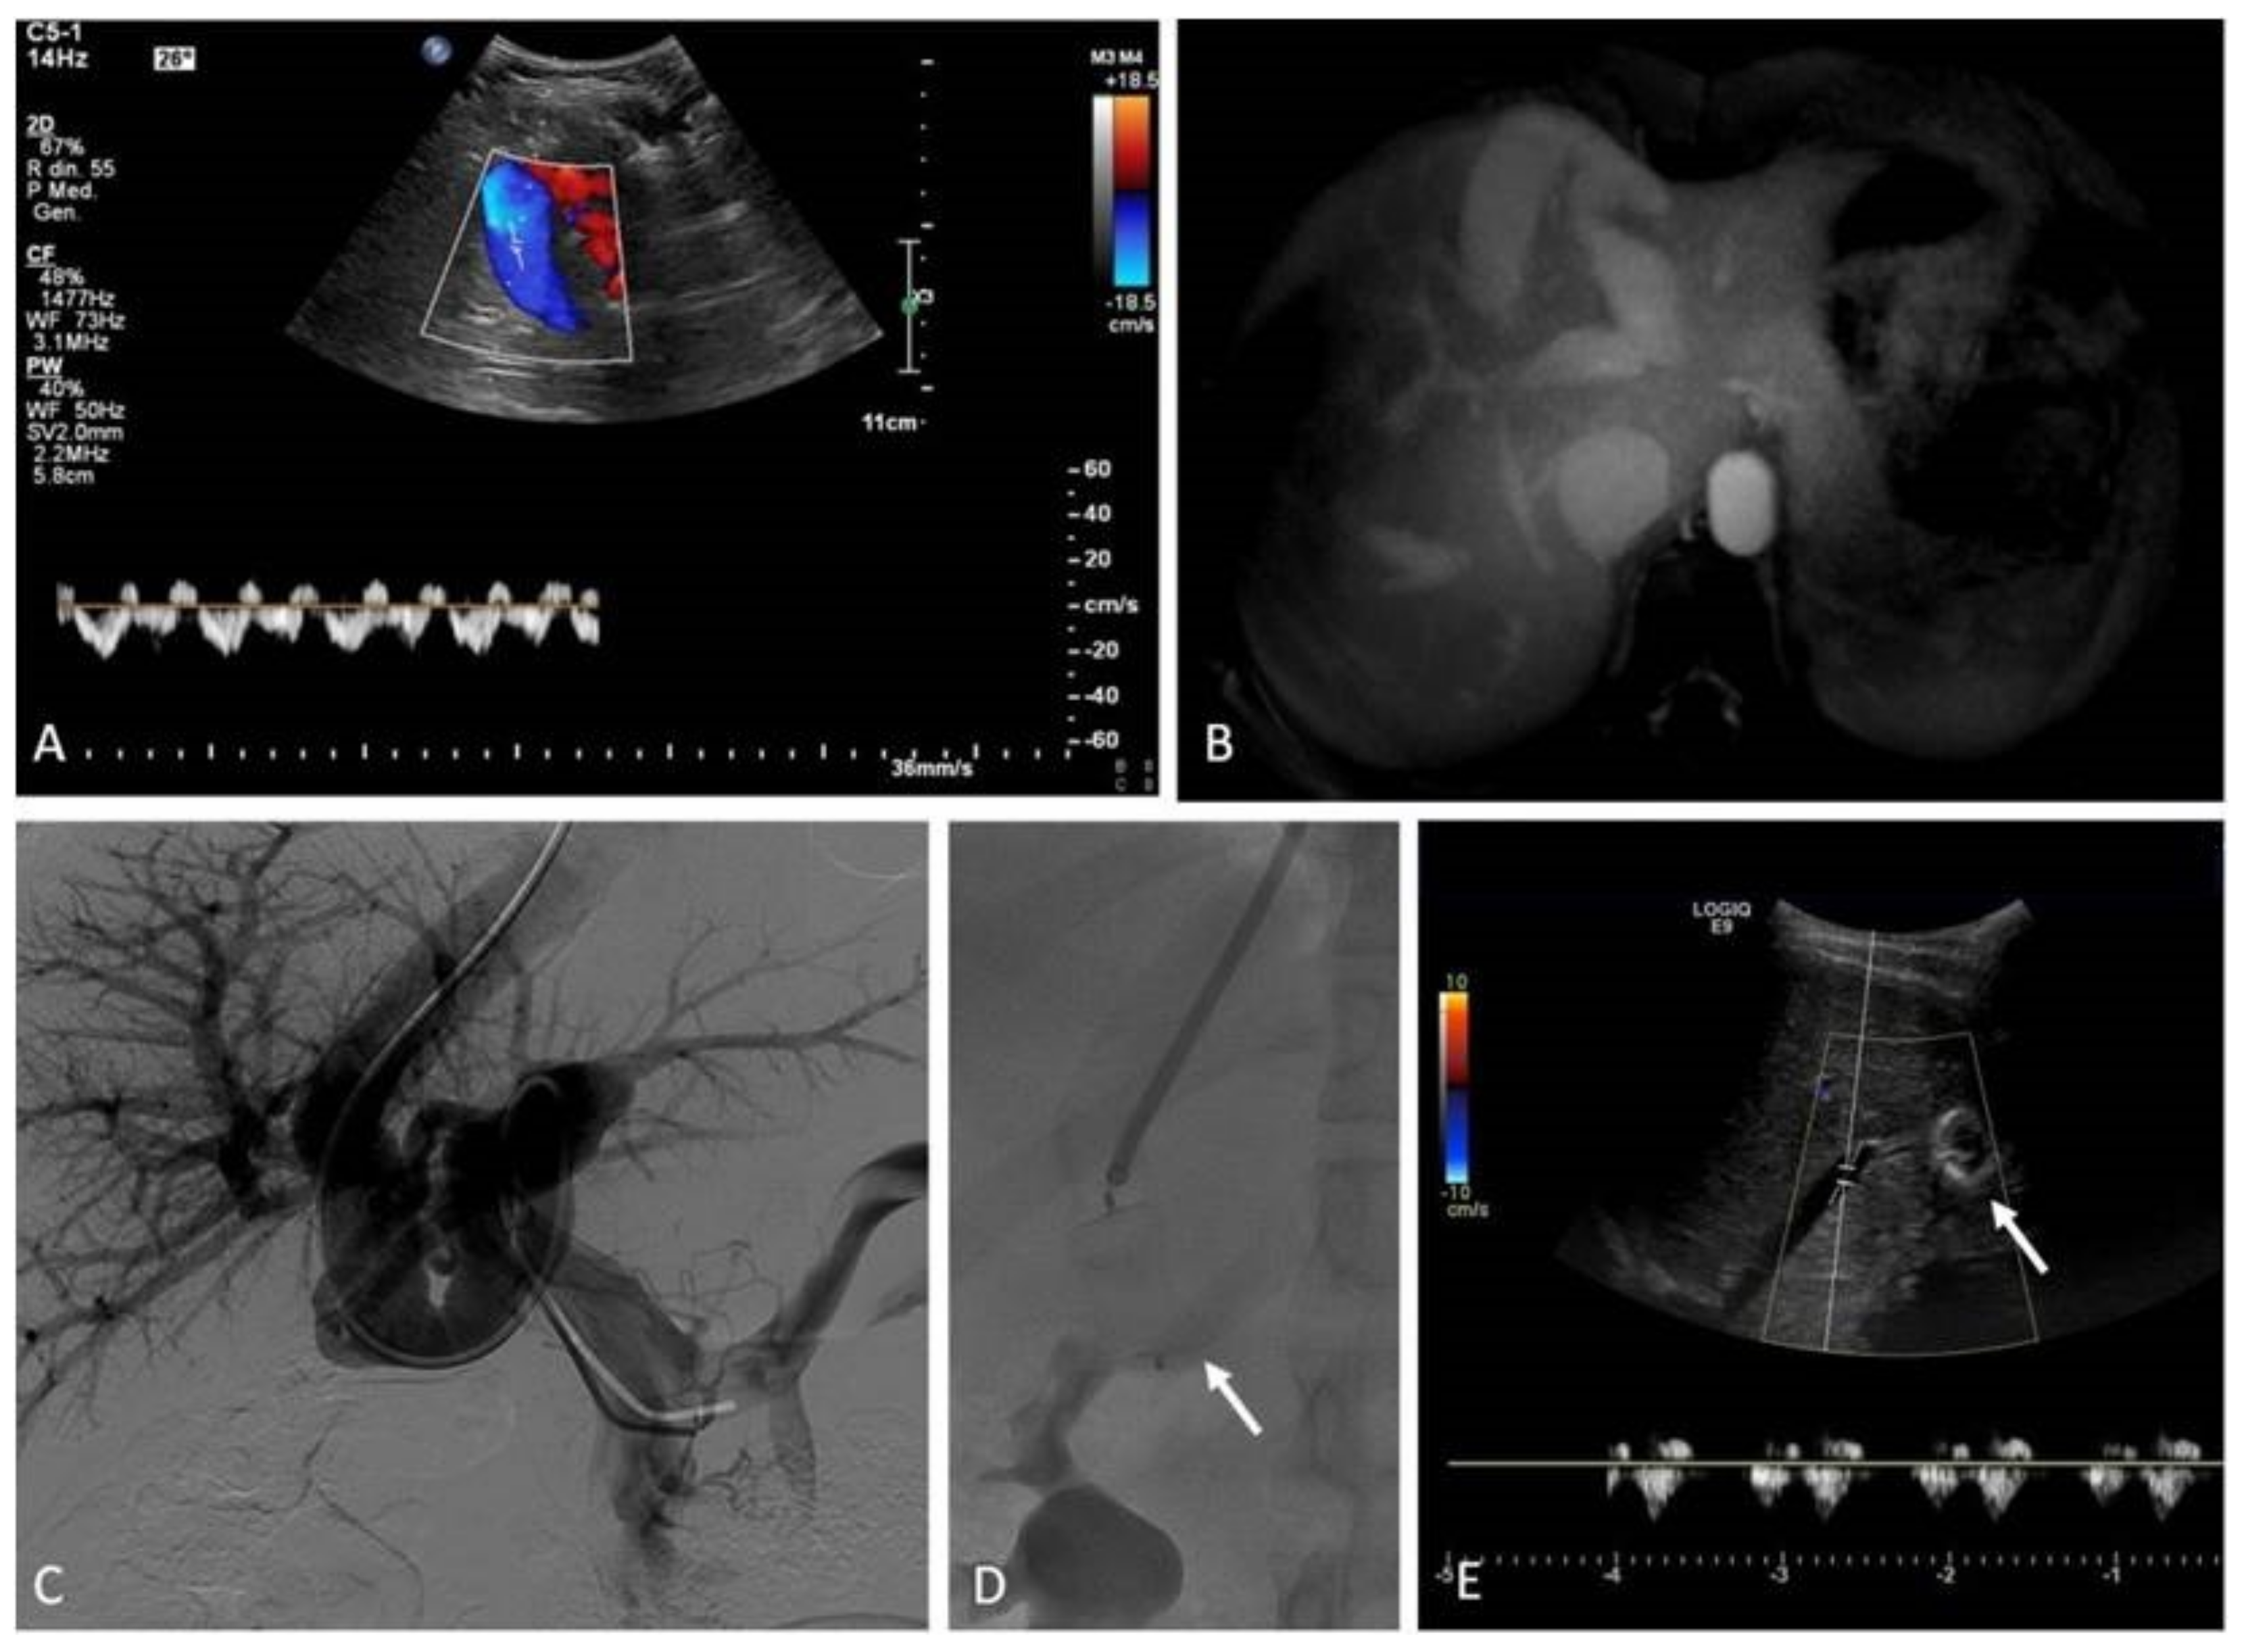

12. Porto-Systemic Shunts

12.1. Indications

12.2. Techniques

12.3. Clinical Outcomes